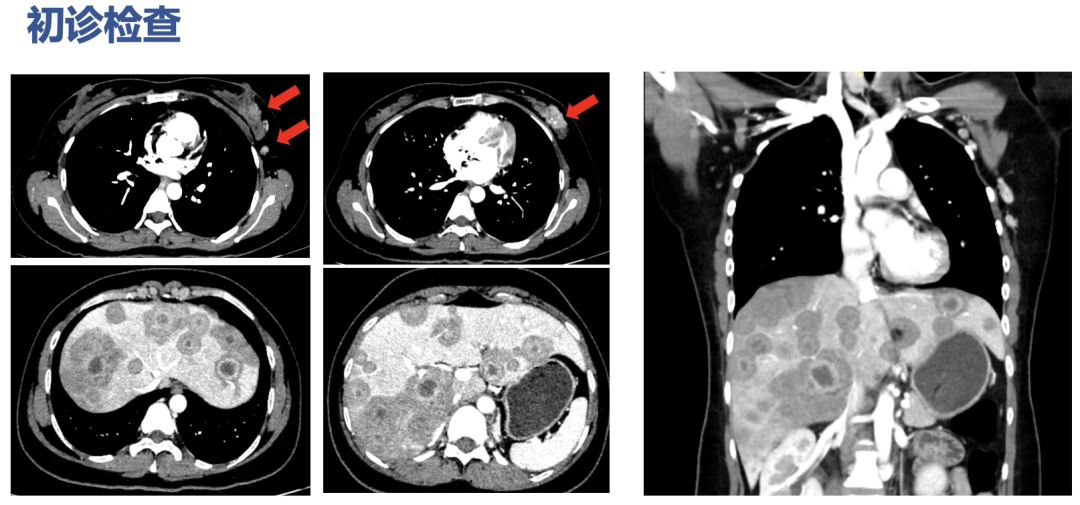

2024.7.22胸上腹部CT

1、左乳外上及外下象限乳腺癌(大小约32.1mm×17.5mm),左侧腋窝、内乳动脉旁淋巴结转移;

2、肝脏弥漫性转移瘤(最大者位于肝S6/7,约96mm×68mm,肿块侵犯右肾上腺);

3、胸椎多发转移瘤